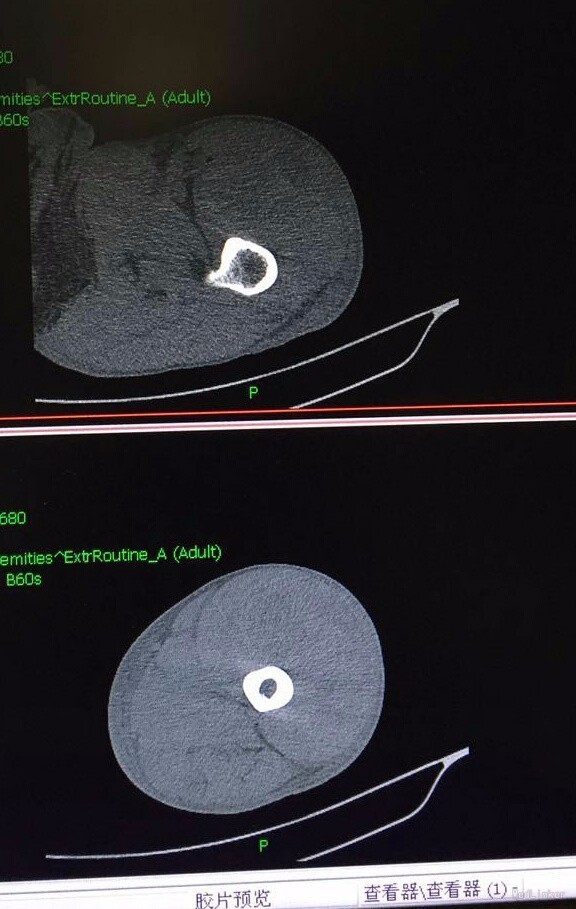

患者男,45岁,因“左髋部摔伤五日余”入院。 患者自诉于五日前步行时不慎摔伤,左髋部着地,伴疼痛,活动受限,遂求治于当地医院,行影像学检查示:左侧股骨颈骨折,给予止痛制动及其他对症支持治疗,治疗后症状无明显好转,遂转入我院,门诊以“左侧股骨颈骨折”收入院。 患者摔伤以来,精神睡眠饮食可,大小便正常,体力一般,体重无明显下降。 既往患者心衰史十余年,新功能三级,口服阿伐他丁、培哚普利、阿司匹林、螺内酯、速尿等控制病情;十年前行瓣膜置换术。其余无特殊。

查体:T:36,2℃,P:86次/分,R:20次/分,BP:135/80mmHg。神志清楚,查体合作,面容正常,全身浅表淋巴结无肿大。心肺腹无异常,双下肢无水肿。生理反射存在,病理反射未引出。 专科情况:患者卧床,不能行走,脊柱生理弯曲存在,未及明显畸形,双上肢皮肤感觉运动可,右下肢皮肤感觉运动可,右髋压痛阴性,右膝压痛阴性,直腿抬高试验90度,四字征阴性,左下肢外旋畸形,较右下肢稍缩短,皮肤感觉可,左髋压痛阳性,左膝压痛阴性,直腿抬高试验及4字征因疼痛不能配合,双侧膝跳反射正常,巴氏征阴性,余生理反射存在,病理反射未引出。 辅检:外院影像学检查是:左股骨颈骨折。我院术前检查无异常,影像学检查见下图。

诊断:左大腿血肿,皮下水肿;心力衰竭(心功能3级) 治疗:止血、脱水、抗心衰、其他对症支持治疗。

这个病人应该是下面医院诊断错了,患者并没有骨折,在我院行止血,脱水等一般治疗。骨折的特有体征有畸形、异常活动、骨擦音或骨擦感,以上三种体征只要发现其中之一,即可确诊。临床症状和体征外,更有影像学检查结果可以确诊,所以骨折的确诊还是比较清楚容易的。